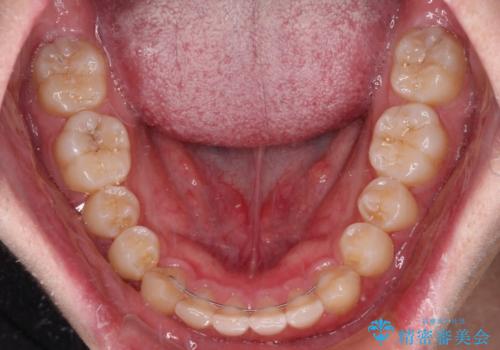

- 矯正装置

- インビザライン

- 前方に傾斜した前歯を気にして来院された患者様です。

強く食いしばってしまう癖があり、下顎前歯に押し出されて上顎前歯が前方へ斜めに突き出している状態でした。

IPR(歯と歯の間を削る)を多用して、インビザラインにて矯正治療を行うこととしました。

口元を引っ込めるためのゴムかけを頑張っていただき、満足のいく上顎前歯の傾斜へ改善することができました。